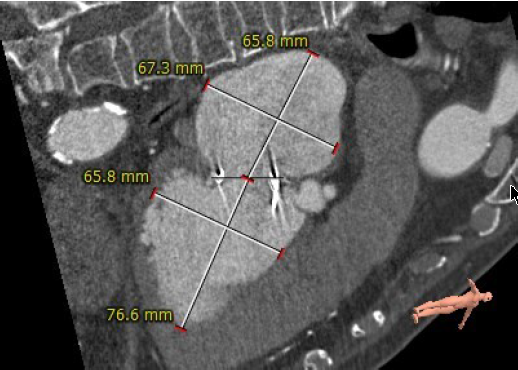

生物瓣瓣环内径23.5mm

生物瓣瓣环外径29.5mm

生物瓣环周围无明显钙化

生物瓣瓣架高度16.1mm